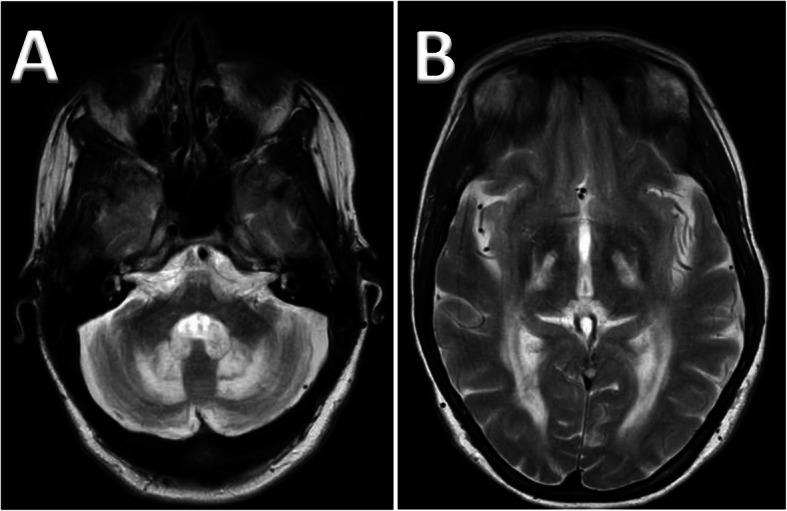

Cerebrotendinous xanthomatosis (CTX) is a rare but treatable neurometabolic disorder of lipid storage and bile acid synthesis. Whilst CTX is said to present with the classic triad of juvenile onset cataracts, tendon xanthomata and progressive ataxia, the diversity of presentation can be such that the diagnosis may be substantially delayed resulting in permanent neurological disability.

A retrospective review of the clinical characteristics and imaging findings of 4 patients with CTX presenting to the Sheffield Ataxia Centre over a period of 25 years.

Although CTX-related symptoms were present from childhood, the median age at diagnosis was 39 years. Only 1 of the 4 cases had tendon xanthomata, only 2 cases had juvenile onset cataracts and 3 had progressive ataxia with one patient presenting with spastic paraparesis. Serum cholestanol was elevated in all 4 patients, proving to be a reliable diagnostic tool. In addition, cholestanol was raised in the CSF of 2 patients who underwent lumbar puncture. Despite treatment with chenodeoxycholic acid (CDCA) and normalization of serum cholestanol, CSF cholestanol remained high in one patient, necessitating increase in the dose of CDCA. Further adjustments to the dose of CDCA in the patient with raised CSF cholestanol resulted in slowing of progression. Two of the patients who have had the disease for the longest continued to progress, one subsequently dying from pneumonia.